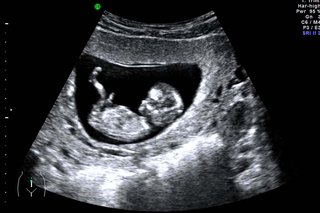

12-week black and white dating scan image of a baby in the womb

Dating scan image

If you're pregnant in England you'll be offered an ultrasound scan at around 10 to 14 weeks of pregnancy. This is called the dating scan. It's used to see how far along in your pregnancy you are and check your baby's development. The scan may also be part of a screening test for Down's syndrome.